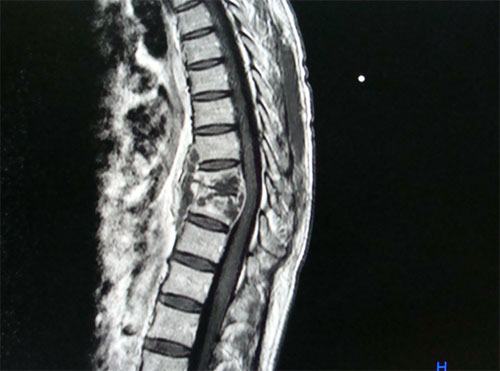

Posttraumatic syringomyelia

Posttraumatic syringomyelia is an uncommon cause of late neurological deterioration in a patient with spinal cord injury. The pathology has received recent attention due to increased physician awareness and the availability of MR imaging. The underlying mechanism is probably local arachnoid scarring and obstruction to CSF flow, followed by seepage of CSF through the Virchow-Robin spaces. Persistent deformity predisposes to formation of posttraumatic syrinx. Anatomical decompression, division of arachnoid scarring, correction of spinal deformity and shunting procedures are measures to arrest the progress of the syrinx.

Click here to read full article